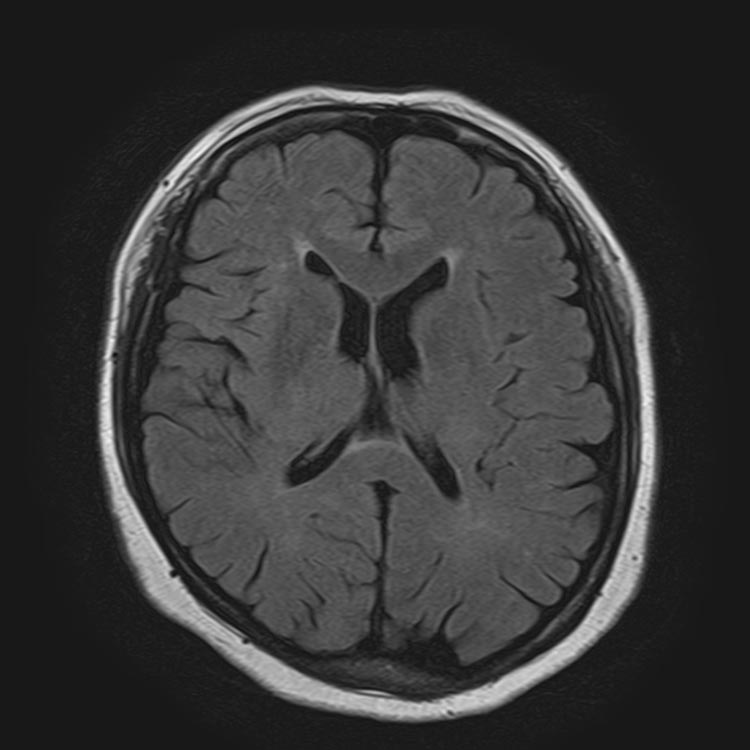

MRI:正常な脳の画像と脳の血管